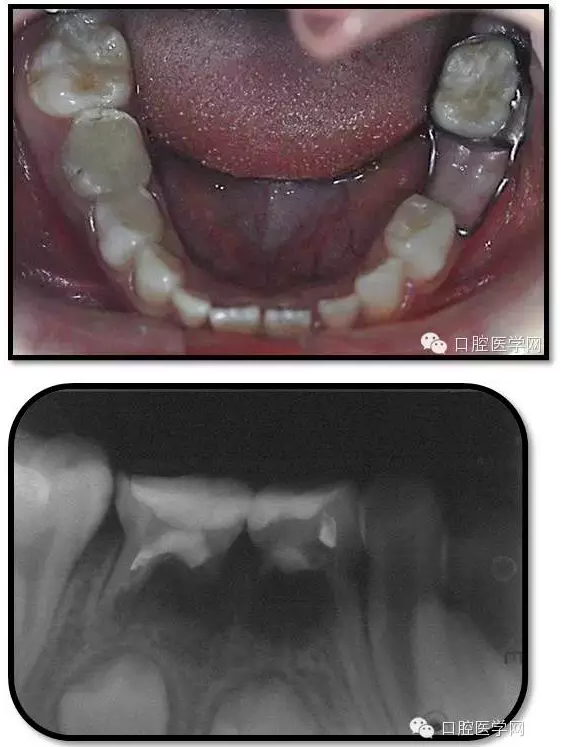

復(fù)查

治療結(jié)束后3個月復(fù)查

復(fù)查:無不適

檢查:口腔衛(wèi)生一般,牙面軟垢菌斑中量。 85O、84DO充填完好,邊緣密合,叩(-),不松,齦無紅腫。

75帶環(huán)絲圈式間隙保持器完好,無松動,無咬合不適。

余牙充填體完好密合,未查及繼發(fā)齲和新發(fā)齲壞。

治療結(jié)束后7個月復(fù)查

85O、84DO充填完好,邊緣密合,叩(-),不松,齦無紅腫。X線:84、85根分歧透射影,44、45骨硬板連續(xù),恒牙胚上方骨板厚約2-3mm。75帶環(huán)絲圈式間隙保持器完好,無松動,無咬合不適。64MO中齲。 64MO中齲去腐凈,自酸蝕,SEBOND,樹脂充填。 口腔衛(wèi)生宣教,囑3個月后復(fù)診。